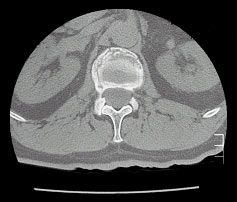

Abb. 2 und 3 von links

Korrekte Lage der Punktionskanülen im gebrochenen Wirbelkörper des Patienten

Beginn der Zementeinspritzung mithilfe einer speziellen Applikationspistole